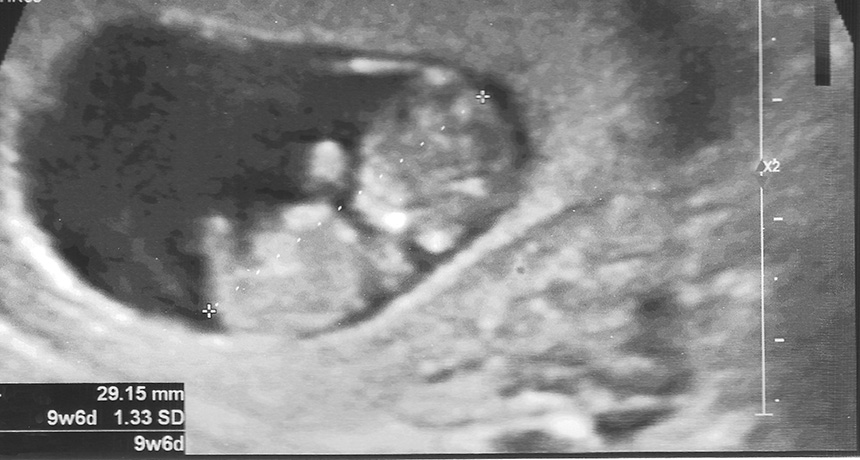

9 week ultrasound

EARLY DAYS  This ultrasound is of a 9-week-old fetus. A new test using fetal cells obtained from a Pap smear can scan a fetus’s genome as early as five weeks.